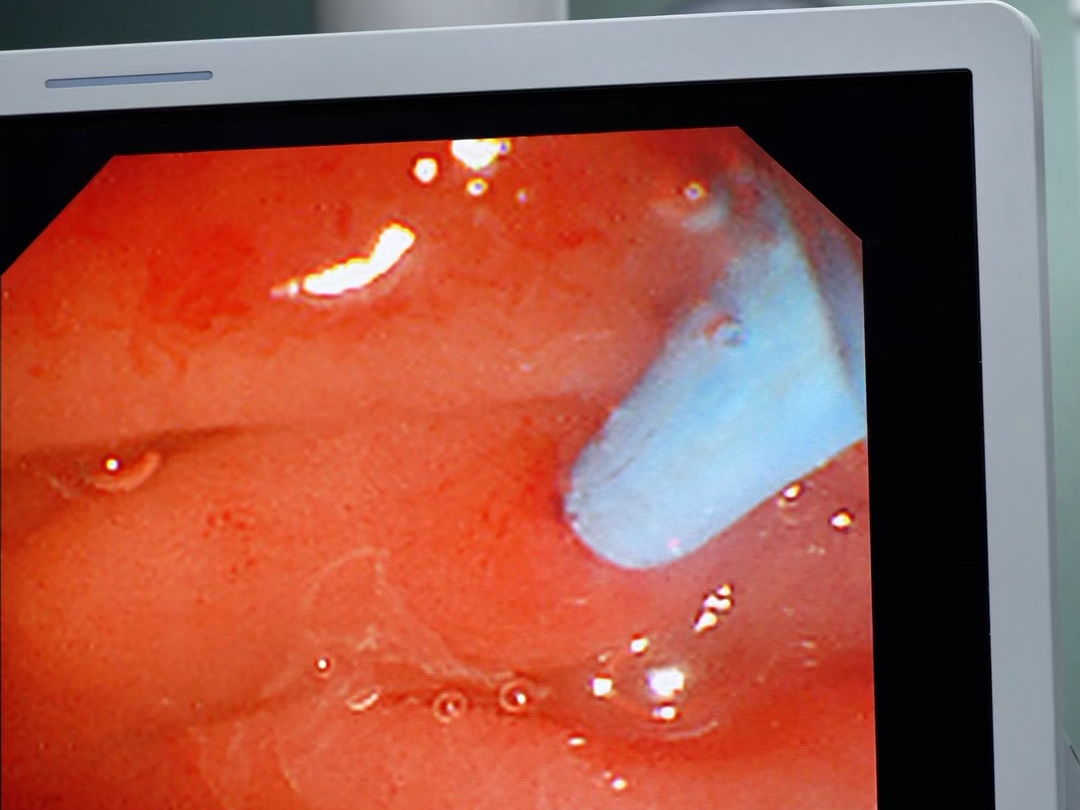

主胰管结石一例

图片尺寸4608x3456